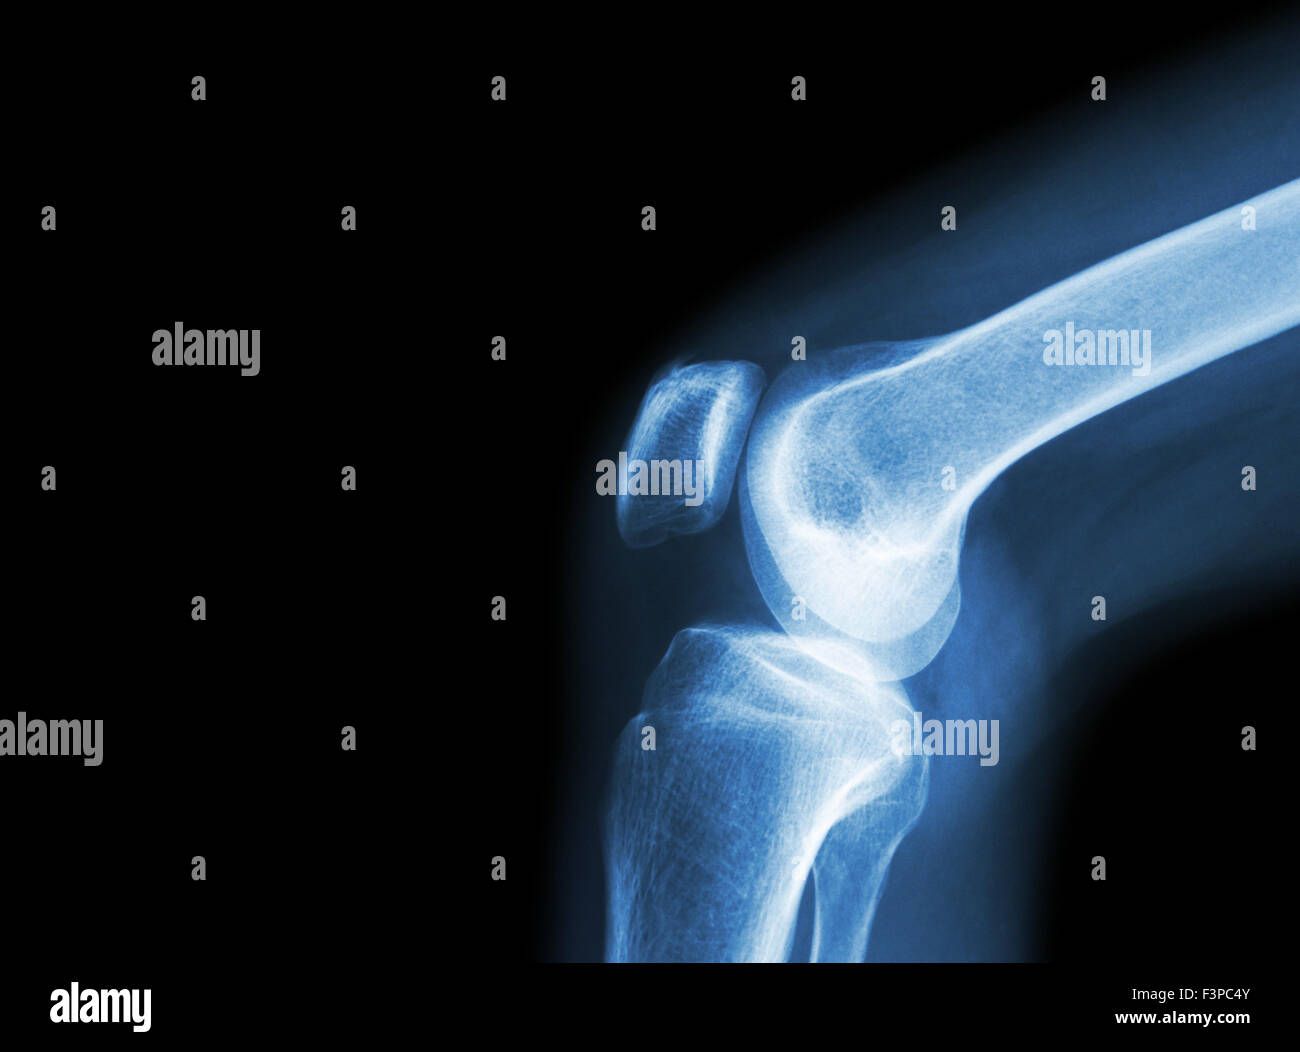

Film x-ray articulation du genou avec l'arthrite ( la goutte, l'arthrite rhumatoïde, l'arthrite septique , l'arthrose du genou ) et la zone vide sous Banque D'Imageshttps://www.alamyimages.fr/image-license-details/?v=1https://www.alamyimages.fr/photo-image-film-x-ray-articulation-du-genou-avec-l-arthrite-la-goutte-l-arthrite-rhumatoide-l-arthrite-septique-l-arthrose-du-genou-et-la-zone-vide-sous-88388299.html

Film x-ray articulation du genou avec l'arthrite ( la goutte, l'arthrite rhumatoïde, l'arthrite septique , l'arthrose du genou ) et la zone vide sous Banque D'Imageshttps://www.alamyimages.fr/image-license-details/?v=1https://www.alamyimages.fr/photo-image-film-x-ray-articulation-du-genou-avec-l-arthrite-la-goutte-l-arthrite-rhumatoide-l-arthrite-septique-l-arthrose-du-genou-et-la-zone-vide-sous-88388299.htmlRFF3PC4Y–Film x-ray articulation du genou avec l'arthrite ( la goutte, l'arthrite rhumatoïde, l'arthrite septique , l'arthrose du genou ) et la zone vide sous

Film x-ray articulation du genou avec l'arthrite ( la goutte, l'arthrite rhumatoïde, l'arthrite septique , l'arthrose du genou ) et la zone vide sous Banque D'Imageshttps://www.alamyimages.fr/image-license-details/?v=1https://www.alamyimages.fr/photo-image-film-x-ray-articulation-du-genou-avec-l-arthrite-la-goutte-l-arthrite-rhumatoide-l-arthrite-septique-l-arthrose-du-genou-et-la-zone-vide-sous-88388298.html

Film x-ray articulation du genou avec l'arthrite ( la goutte, l'arthrite rhumatoïde, l'arthrite septique , l'arthrose du genou ) et la zone vide sous Banque D'Imageshttps://www.alamyimages.fr/image-license-details/?v=1https://www.alamyimages.fr/photo-image-film-x-ray-articulation-du-genou-avec-l-arthrite-la-goutte-l-arthrite-rhumatoide-l-arthrite-septique-l-arthrose-du-genou-et-la-zone-vide-sous-88388298.htmlRFF3PC4X–Film x-ray articulation du genou avec l'arthrite ( la goutte, l'arthrite rhumatoïde, l'arthrite septique , l'arthrose du genou ) et la zone vide sous

Film x-ray articulation du genou avec l'arthrite ( la goutte, l'arthrite rhumatoïde, l'arthrite septique , l'arthrose du genou ) et la zone vide sous Banque D'Imageshttps://www.alamyimages.fr/image-license-details/?v=1https://www.alamyimages.fr/photo-image-film-x-ray-articulation-du-genou-avec-l-arthrite-la-goutte-l-arthrite-rhumatoide-l-arthrite-septique-l-arthrose-du-genou-et-la-zone-vide-sous-88388301.html

Film x-ray articulation du genou avec l'arthrite ( la goutte, l'arthrite rhumatoïde, l'arthrite septique , l'arthrose du genou ) et la zone vide sous Banque D'Imageshttps://www.alamyimages.fr/image-license-details/?v=1https://www.alamyimages.fr/photo-image-film-x-ray-articulation-du-genou-avec-l-arthrite-la-goutte-l-arthrite-rhumatoide-l-arthrite-septique-l-arthrose-du-genou-et-la-zone-vide-sous-88388301.htmlRFF3PC51–Film x-ray articulation du genou avec l'arthrite ( la goutte, l'arthrite rhumatoïde, l'arthrite septique , l'arthrose du genou ) et la zone vide sous

Film x-ray articulation du genou avec l'arthrite ( la goutte, l'arthrite rhumatoïde, l'arthrite septique , l'arthrose du genou ) et la zone vide sous Banque D'Imageshttps://www.alamyimages.fr/image-license-details/?v=1https://www.alamyimages.fr/photo-image-film-x-ray-articulation-du-genou-avec-l-arthrite-la-goutte-l-arthrite-rhumatoide-l-arthrite-septique-l-arthrose-du-genou-et-la-zone-vide-sous-88388300.html

Film x-ray articulation du genou avec l'arthrite ( la goutte, l'arthrite rhumatoïde, l'arthrite septique , l'arthrose du genou ) et la zone vide sous Banque D'Imageshttps://www.alamyimages.fr/image-license-details/?v=1https://www.alamyimages.fr/photo-image-film-x-ray-articulation-du-genou-avec-l-arthrite-la-goutte-l-arthrite-rhumatoide-l-arthrite-septique-l-arthrose-du-genou-et-la-zone-vide-sous-88388300.htmlRFF3PC50–Film x-ray articulation du genou avec l'arthrite ( la goutte, l'arthrite rhumatoïde, l'arthrite septique , l'arthrose du genou ) et la zone vide sous